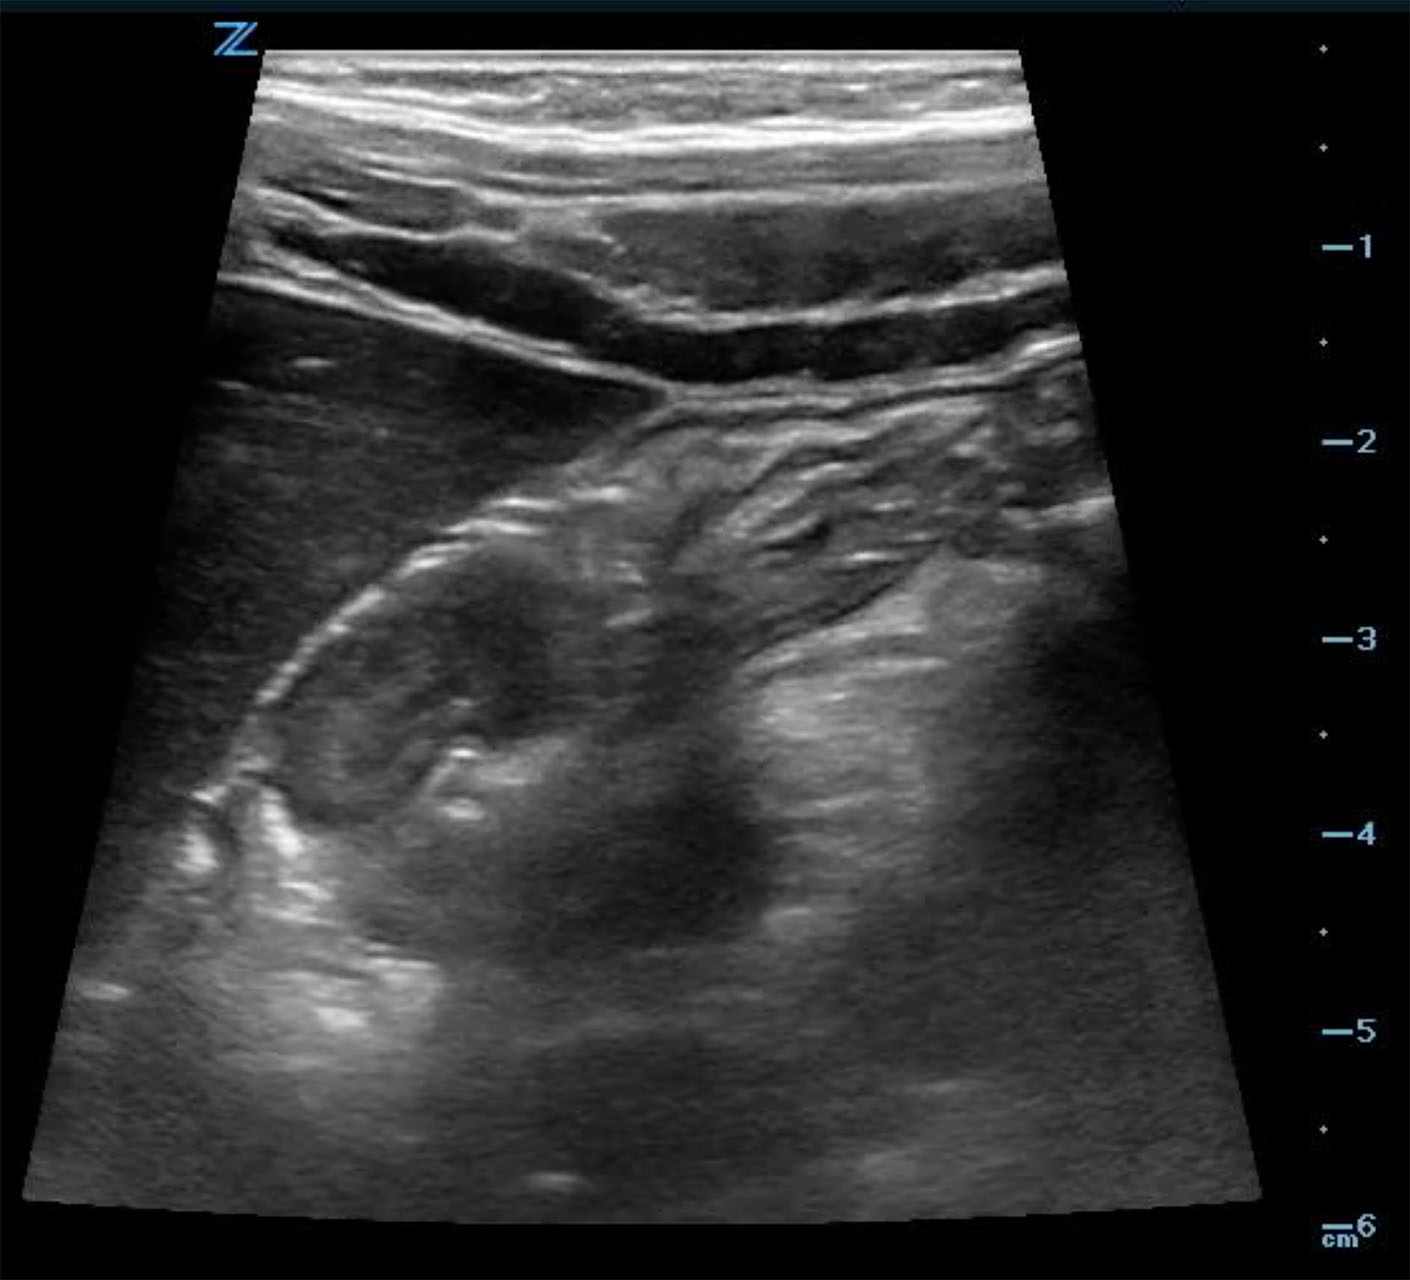

- In the long axis, a kidney-shaped mass, which is often called the pseudokidney sign, is seen. This is an oblique view of the invaginated bowel. (Fig. 6a)

- Figure 6a. Image in long axis of ileocolic intussusception